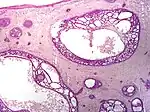

| Cystic basal-cell carcinoma | Morphologically characterized by dome-shaped, blue-gray cystic nodules.[2] | ![]() | |

| Micronodular basal-cell carcinoma | Small and closely spaced nests. | ![]() | |